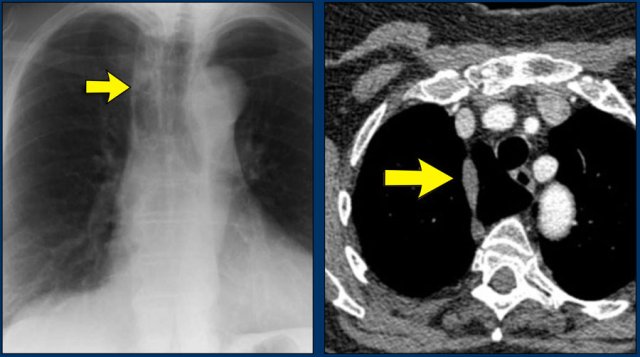

Another common cause of displacement of the azygoesophageal line is subcarinal lymphadenopathy.

Notice the displacement of the upper part of the azygoesophageal line on the chest x-ray in the area below the carina.

This is the result of massive lymphadenopathy in the subcarinal region (station 7).

There are also nodes on the right of the trachea displacing the right paratracheal line.

On the PET we can appreciate the massive lymphadenopathy far better than on the CXR.

There are also lymphomas in the neck.

this is an important finding, since these nodes are accessible for biopsy.

Here we see a CT-image.

The azygoesophageal recess is displaced by lymph nodes that compress the left atrium.

The final diagnosis of small cel lungcancer was made through a biopsy of a lymphnode in the neck.